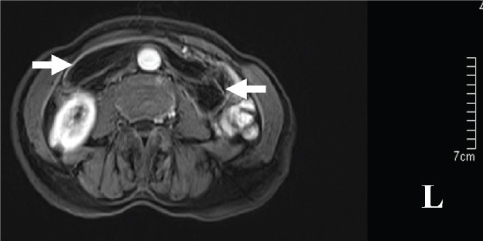

A 67-year-old woman was transferred to our hospital with one-day history of abdominal pain, vomit and constipation. She had a five years history of epigastric fullness and intermittent, upper abdominal pain in the past. CT revealed intestinal obstruction and hypodense lesions with CT value of -64 housefield units (HU) to -138 HU located from the descending part of the duodenum to the proximal jejunum, which was suggestive of lipomas [Table/Fig-1]. MR showed fat-containing mass lesions and the masses were high-intensity on T1-weighted and intermediately intensity on T2-weighted images [Table/Fig-2], with a drop in signal on T1 and T2-weighted fat-suppressed images [Table/Fig-3], consistent with a diagnosis of duodenal lipomas.

Axial T1-weighted MRI shows a well-demarcated, hyperintense mass (arrow).

Because early symptoms are often nonspecific and vague, it is important to keep the diagnosis of DL in the differential diagnosis of obscure abdominal pain or gastrointestinal tract bleeding. Despite consideration of this diagnosis, it can still be difficult to confirm. Diagnosis can be established by radiological, endoscopic or operative means. Current imaging modalities, such as CT and MRI can provide an accurate diagnosis [16]. DLs appear on CT as a well-circumscribed hypodense lesion with a density ranging from -60 to -120 HU [59]. As fat suppression techniques effectively reduce the macroscopic fat signal, they are preferred in order to diagnose lipomas with MR [16]. Lipomas have high-intensity on T1-weighted images and usually present intermediate intensity on T2-weighted images. The loss of signal on fat-suppressed images enables the final diagnosis by MRI [16]. Though CT and MRI are helpful in diagnosis but these are unable to precisely locate the origin of the lesion. Direct visualization at endoscopy provides the clues about the nature of the tumour. In most cases, endoscopy has become the choice for diagnosis, either by the appearance of a pedunculate mass of fat or of a lesion stretching the sub-mucosa and when the mucosa is uncovered the shiny yellow colour of the lipoma becomes apparent “the naked fat sign” [44]. But it is generally insufficient in making a definitive diagnosis by endoscopy if the lipoma is submucosal or subserol. EUS is effective to provide information about the original layer, echogenicity, the depth and invasion [34]. The typical EUS findings for DLs are intense homogeneous hyperechoic mass originating from the submucosa, with echo attenuation behind and/or inside the rear area [58]. If the lipoma is within reach of the endoscope, a biopsy forcep can be used to prove the diagnosis. Before biopsy of the putative lipoma, however, the diagnosis might be suspected. The “naked fat sign”, “pillow sign” and “tenting sign” [17] have been said to be pathognomonic.